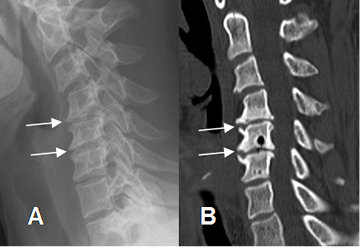

Fig 43. Cambios degenerativos.

A: Rx lateral y B: TAC reconstrucción sagital. Formación de osteofitos en la parte anterior de los cuerpos cervicales, por proceso degenerativo.